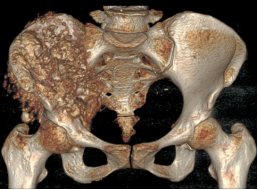

术后影像

据主刀医师徐生林介绍,本例病例将整个右侧半骨盆Ⅰ+Ⅱ+Ⅲ+Ⅳ区(累及骶骨)进行整块切除,同时切除肿瘤覆盖的部分骶骨。3D打印假体所有骨接触界面均设计为骨整合结构,有利于骨长入和骨盆假体的永久稳定。耻、坐骨结构不规则,因此设计组配式结构,有利于术中操作,极大地方便了术中的假体安装。

3D打印技术的出现,使骨肿瘤的精准切除成为了可能,3D打印制造技术能够很好地适形匹配肿瘤切除后的骨结构,通过假体-骨接触面的特殊制造技术达到假体-骨整合,解决了骨肿瘤切除后大段骨关节缺损的重建问题,在生物力学重建和功能重建上比常规假体优势明显。3D打印假体使骨肿瘤切除重建进入“个性化、精准化、私人定制”时代。